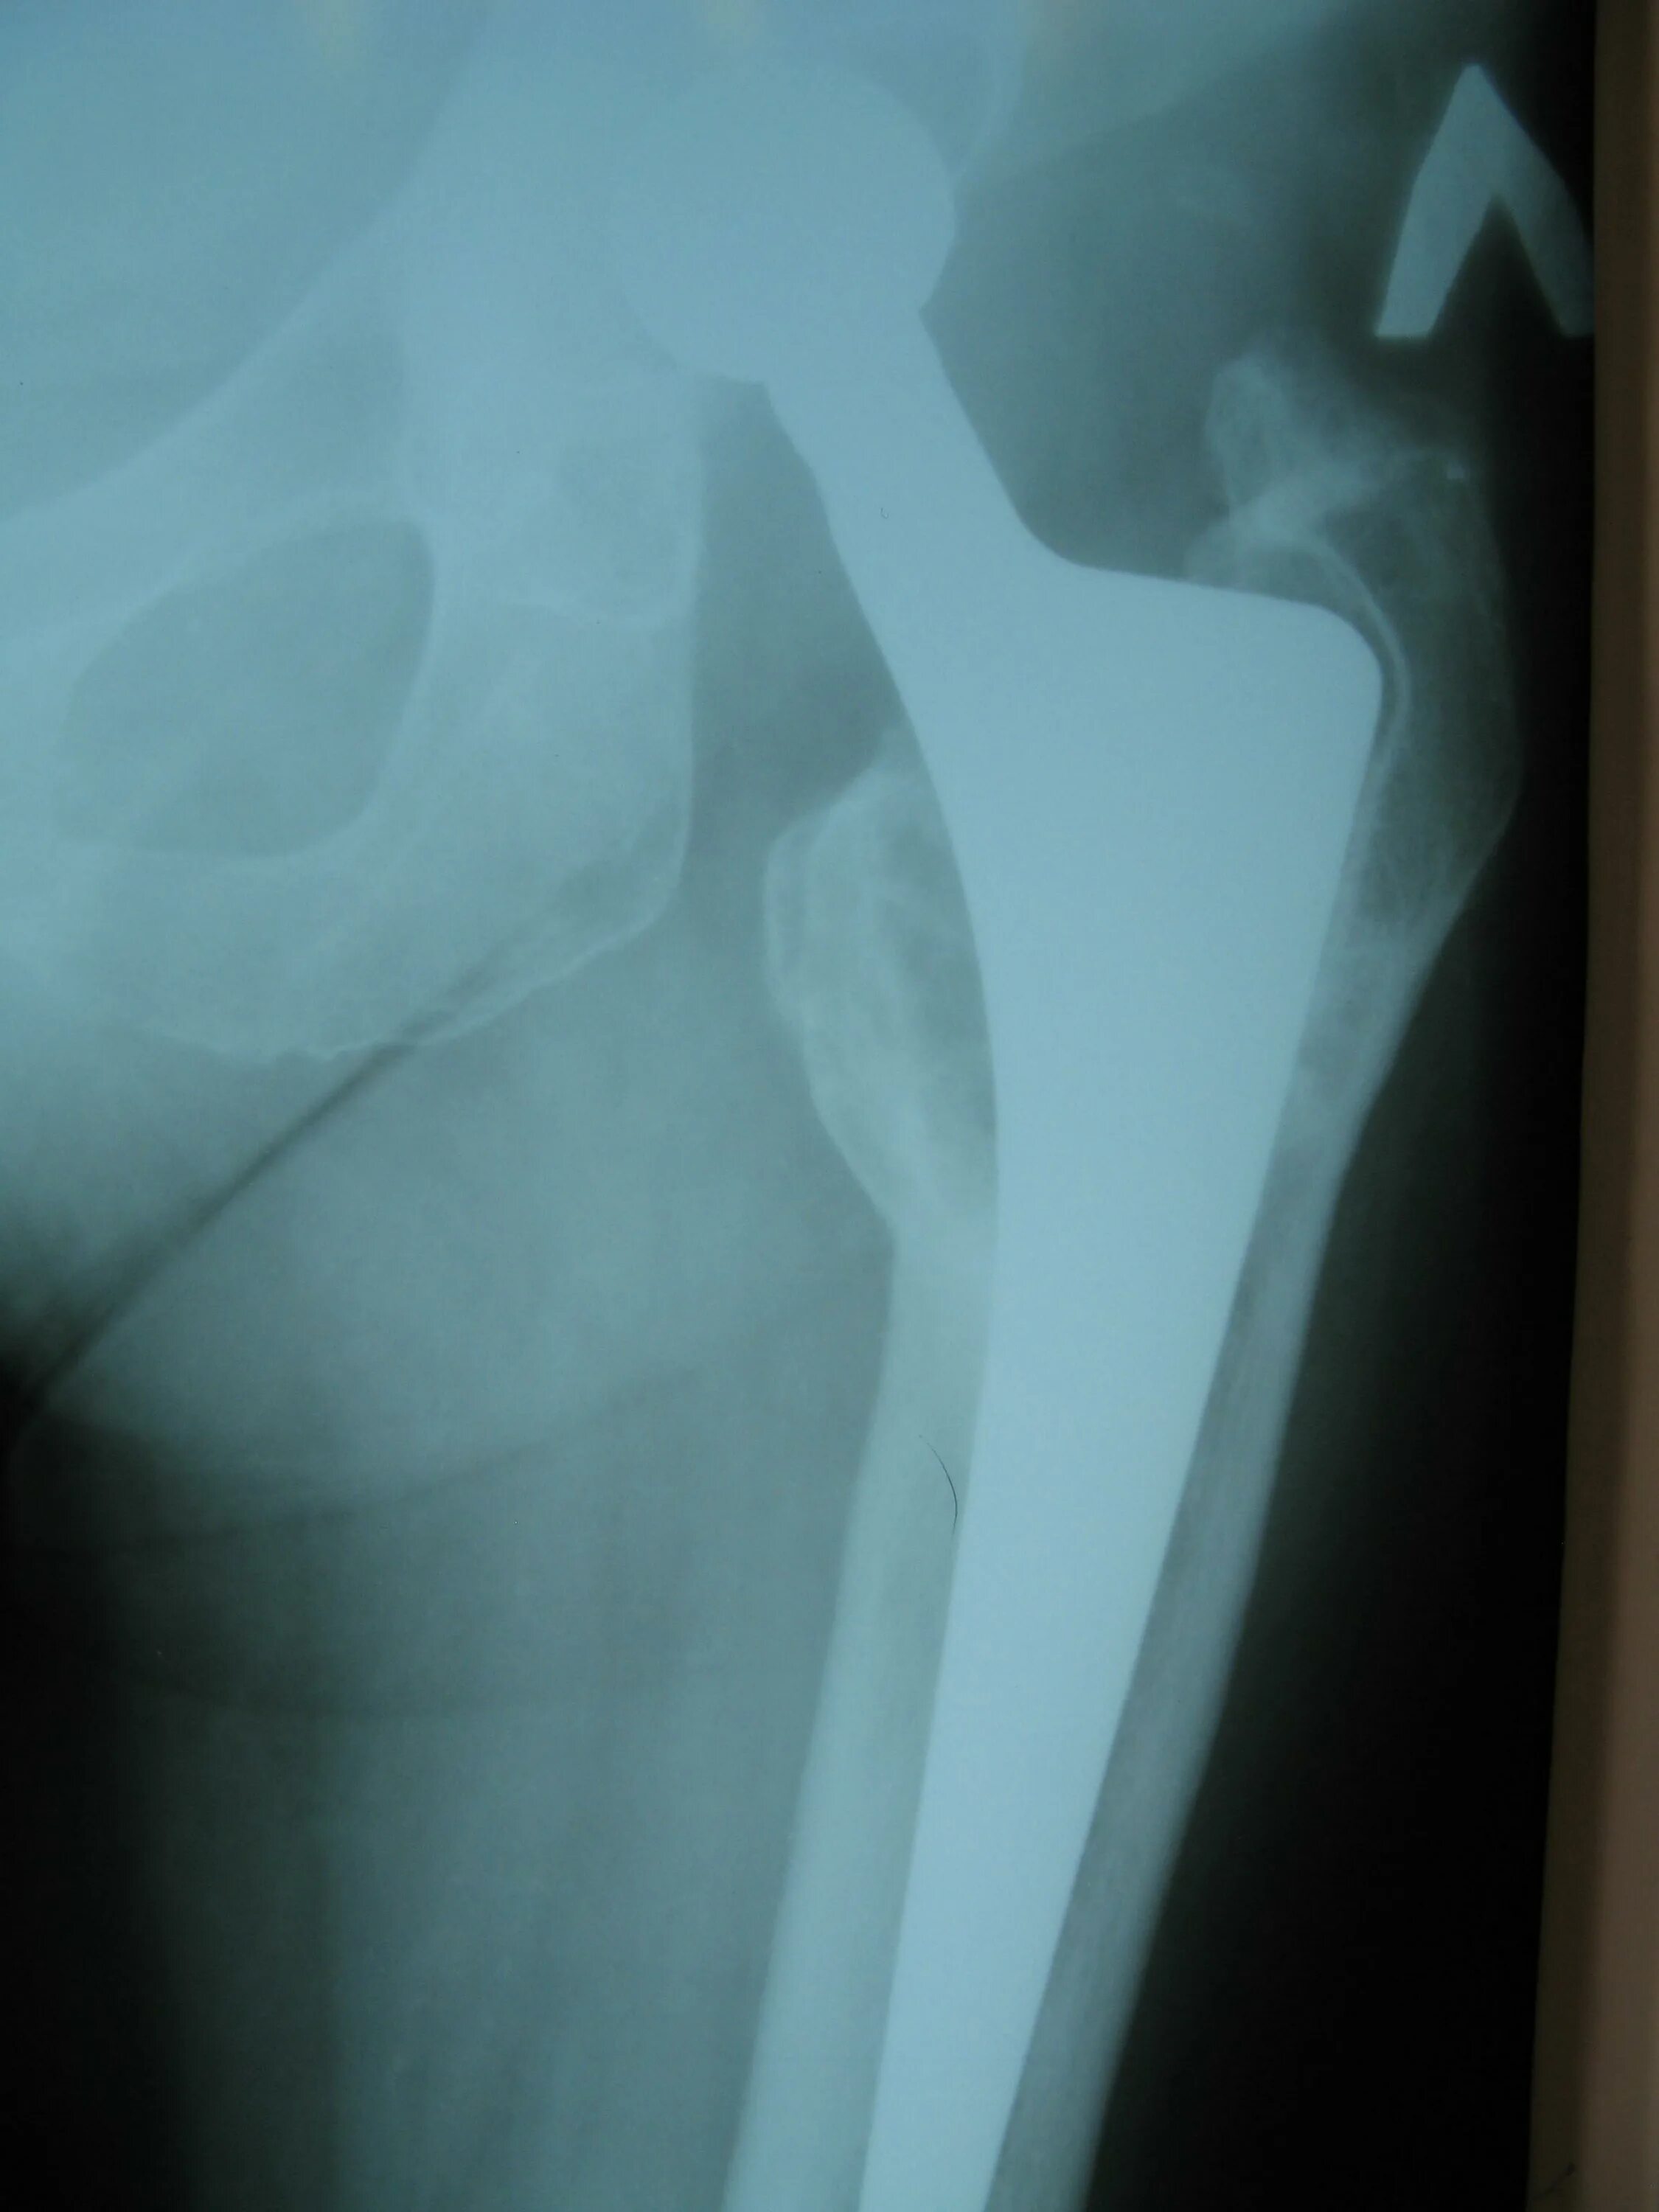

Эндопротез сустава мкб 10